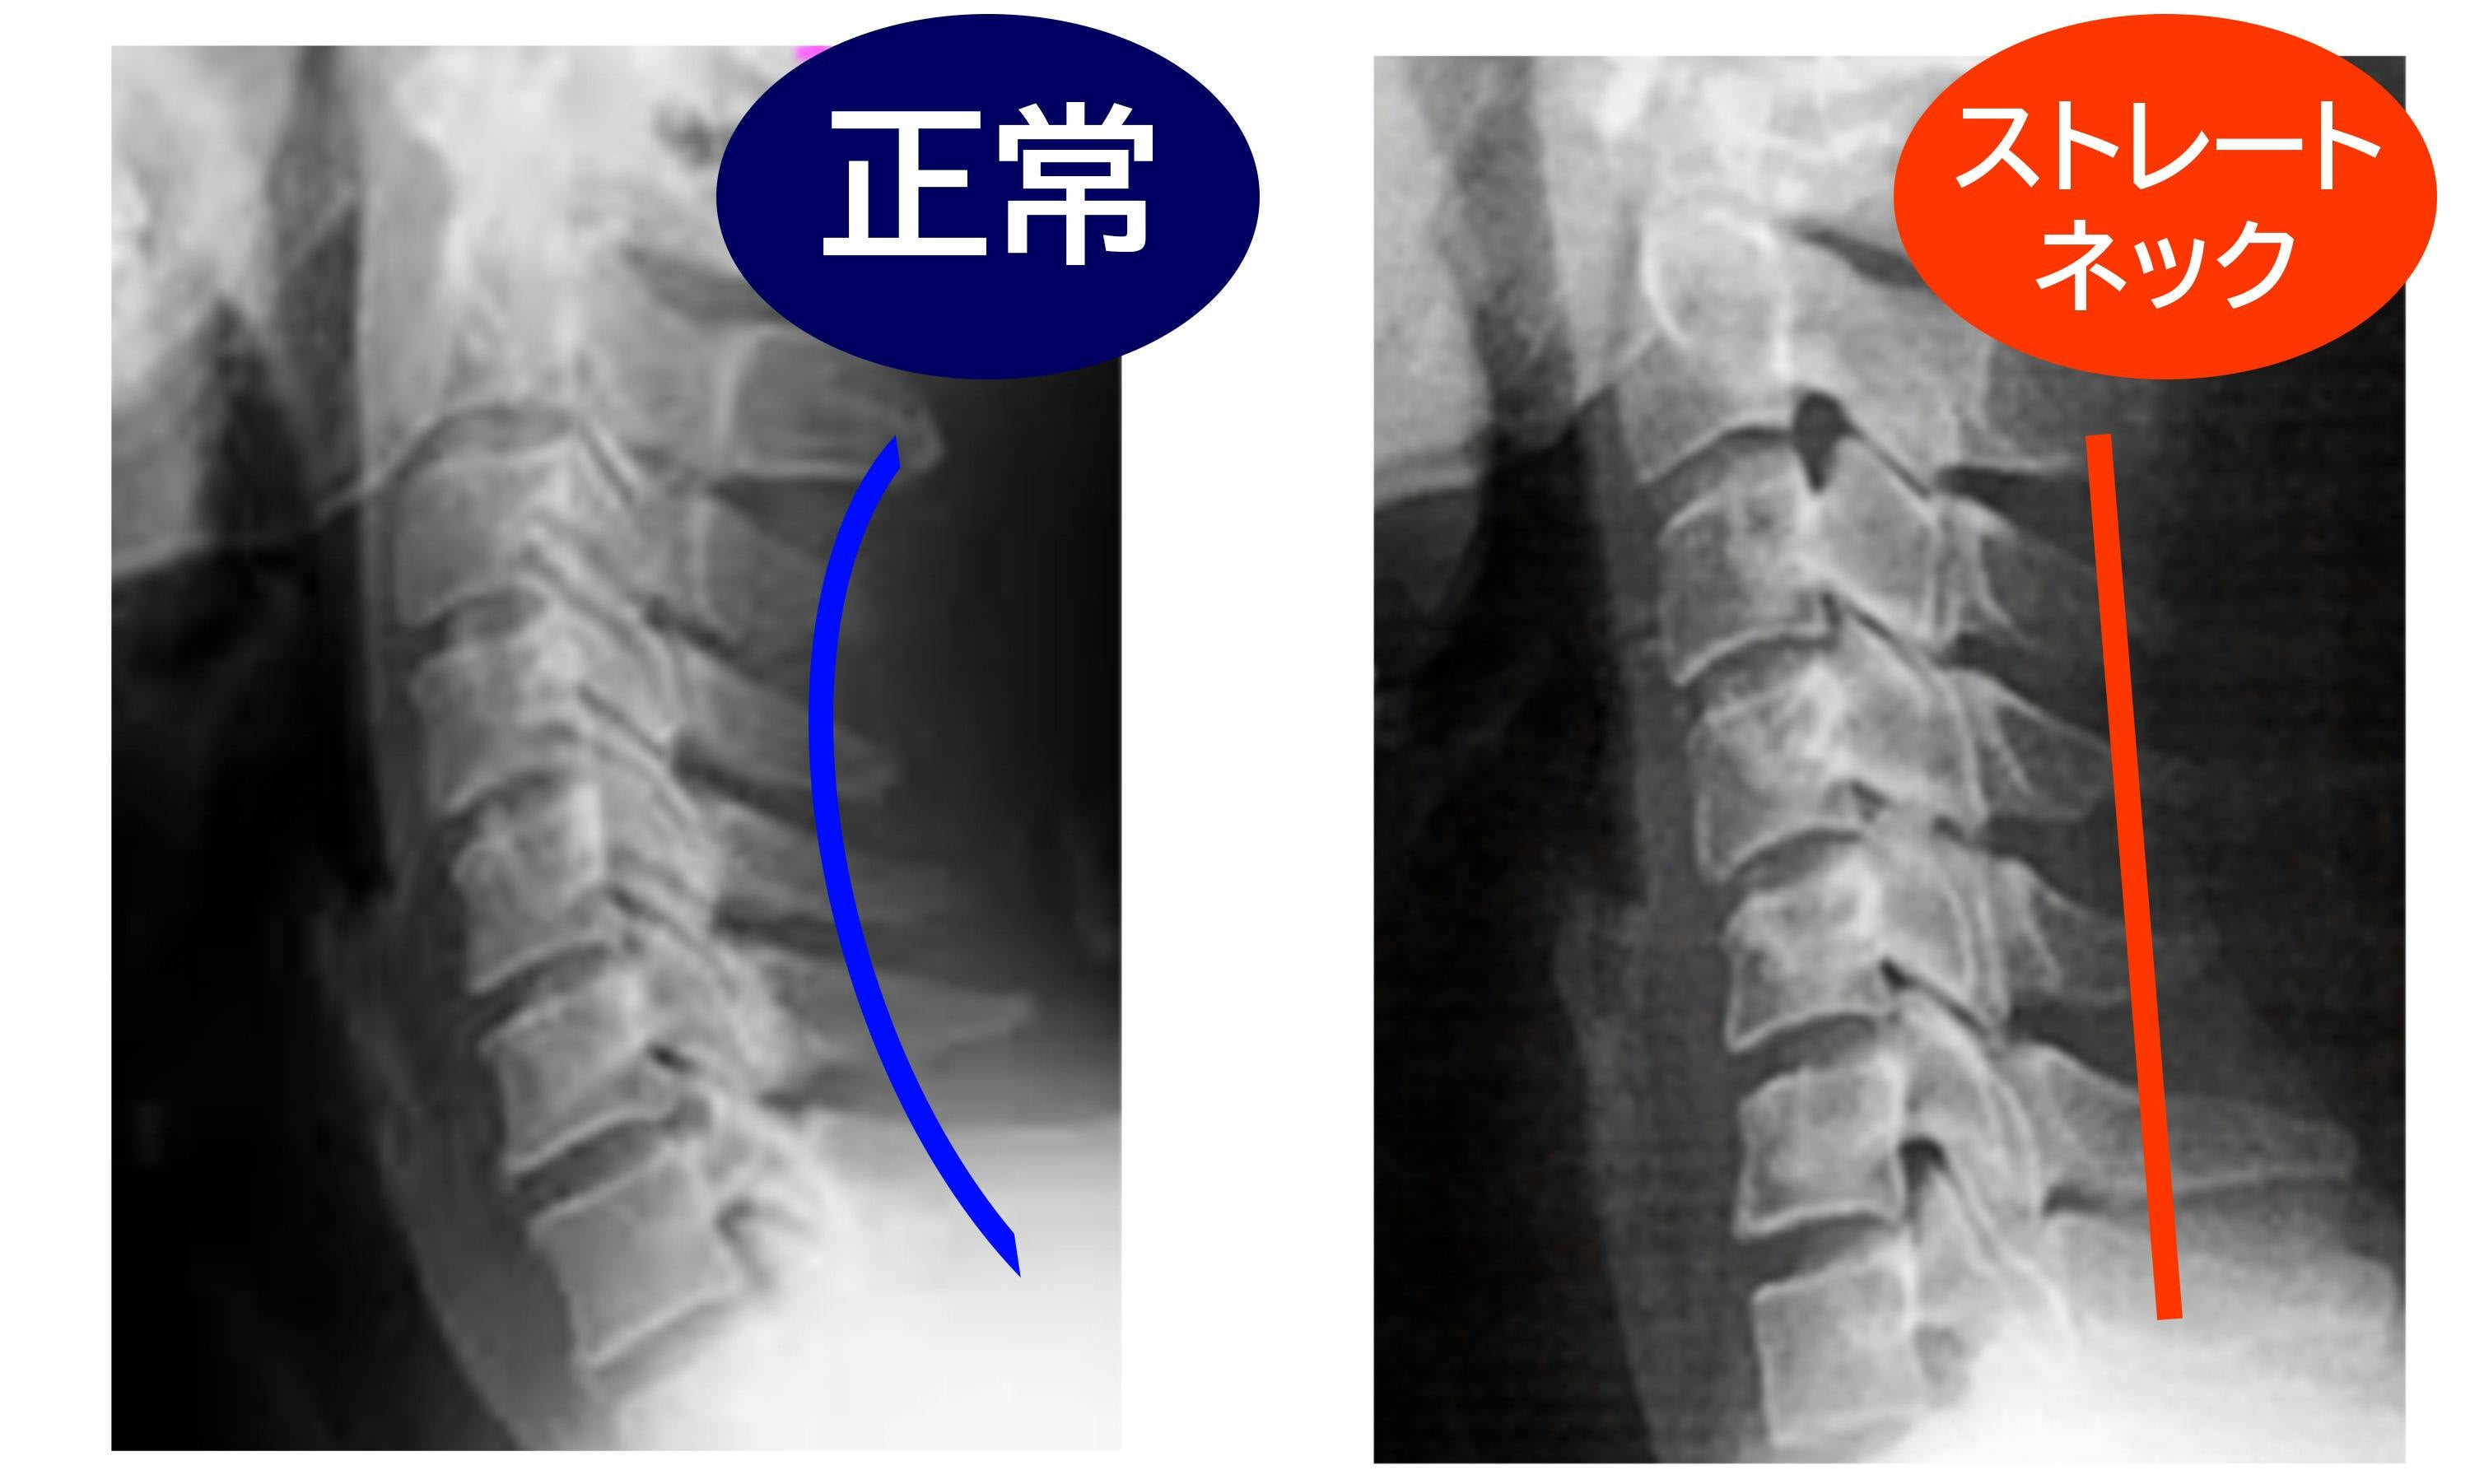

A: 頸椎太郎は、床に置いてその上に仰向けになり、首をサポートするように位置を調整して使用します。毎日8分間使用することで、首や肩の筋肉をストレッチし、リラックスさせることができます。ストレートネックの改善や、正常な頚椎のカーブを取り戻すことを目指しています。